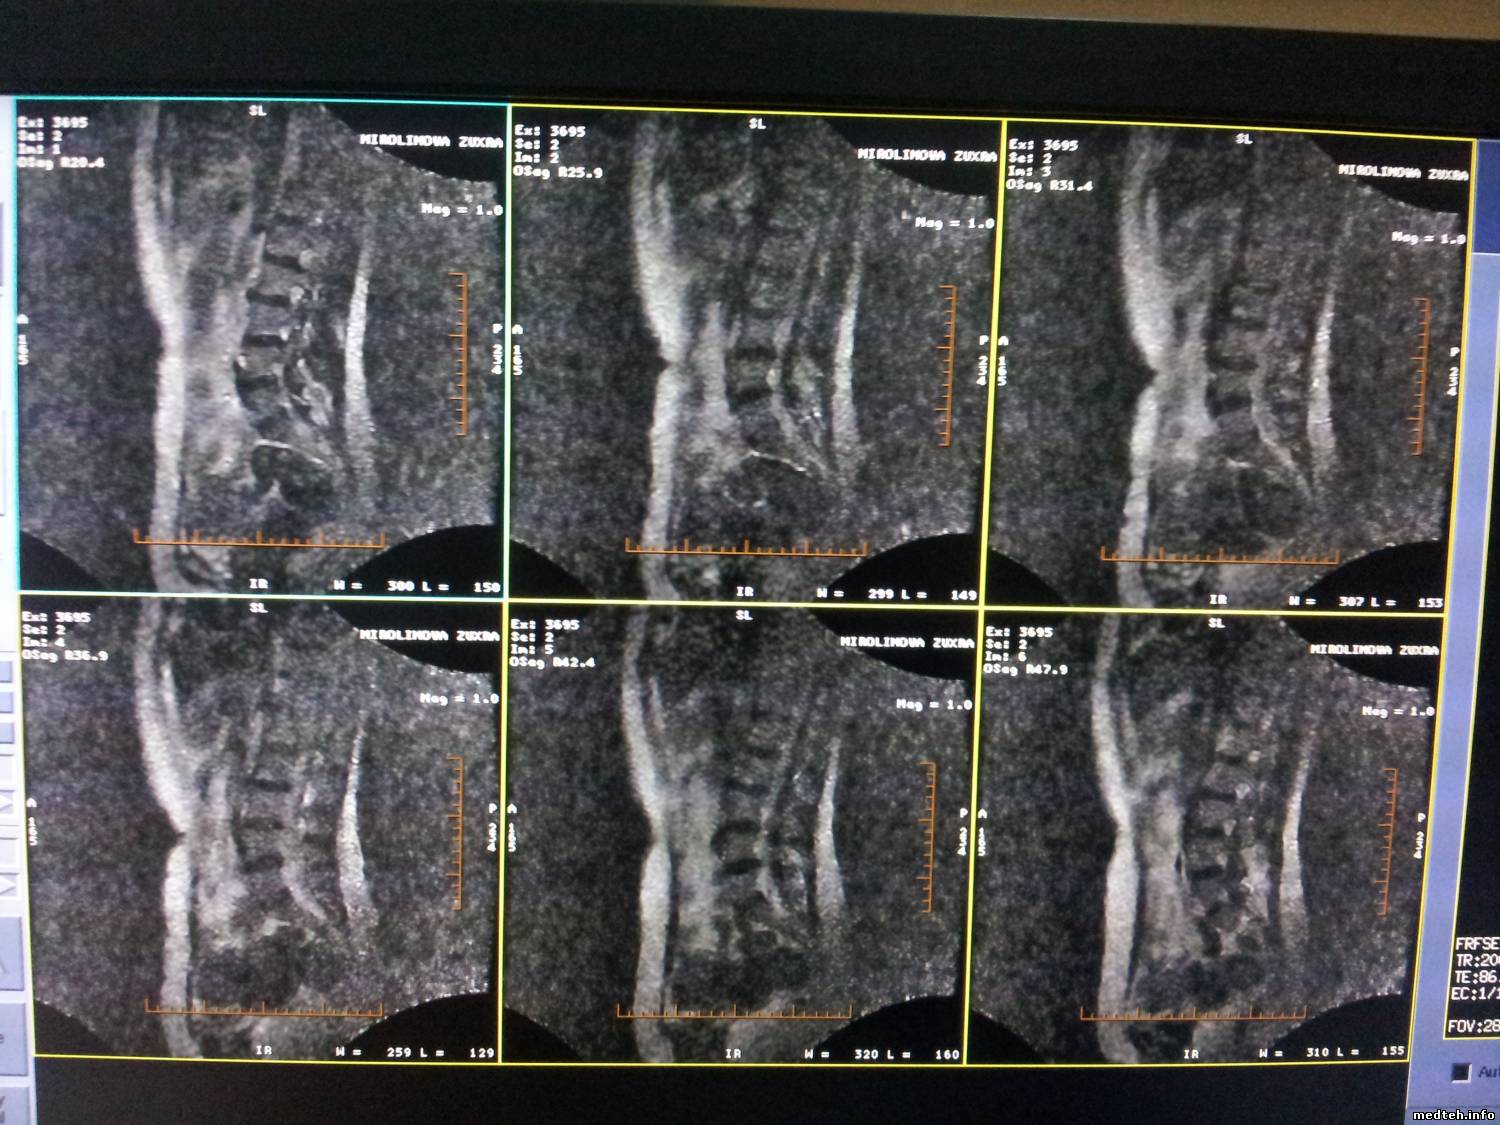

доброе время суток. прошу не судить строго. проблема в катушек body flex II L. после сканирования полного человека качество изображения снизилось. с пера сканировала то хорошо то плохо затем качество становилось все хуже и хуже. такое ощущение что отпоялись контакты. что надо делать. благодарен за любой совет.

2485999.jpg (223.5 Kb)

получилось неправильно закреплял good вот фото коила

Неоднократно приходилось ремонтировать данную катушку. Проблемы возникают из за поломки медных проводников антенны в местах изгиба.Лечилось запаиванием проводников,лучше многожильным проводом,так как просто запайка через некоторое время опять лопается.Разрежьте ткань катушки и там все увидите.Ломаются как правило наружные проводники. Удачи.

hobot111 большое спасибо за совет. поломка была в местах изгиба. пропоял и все заработало good